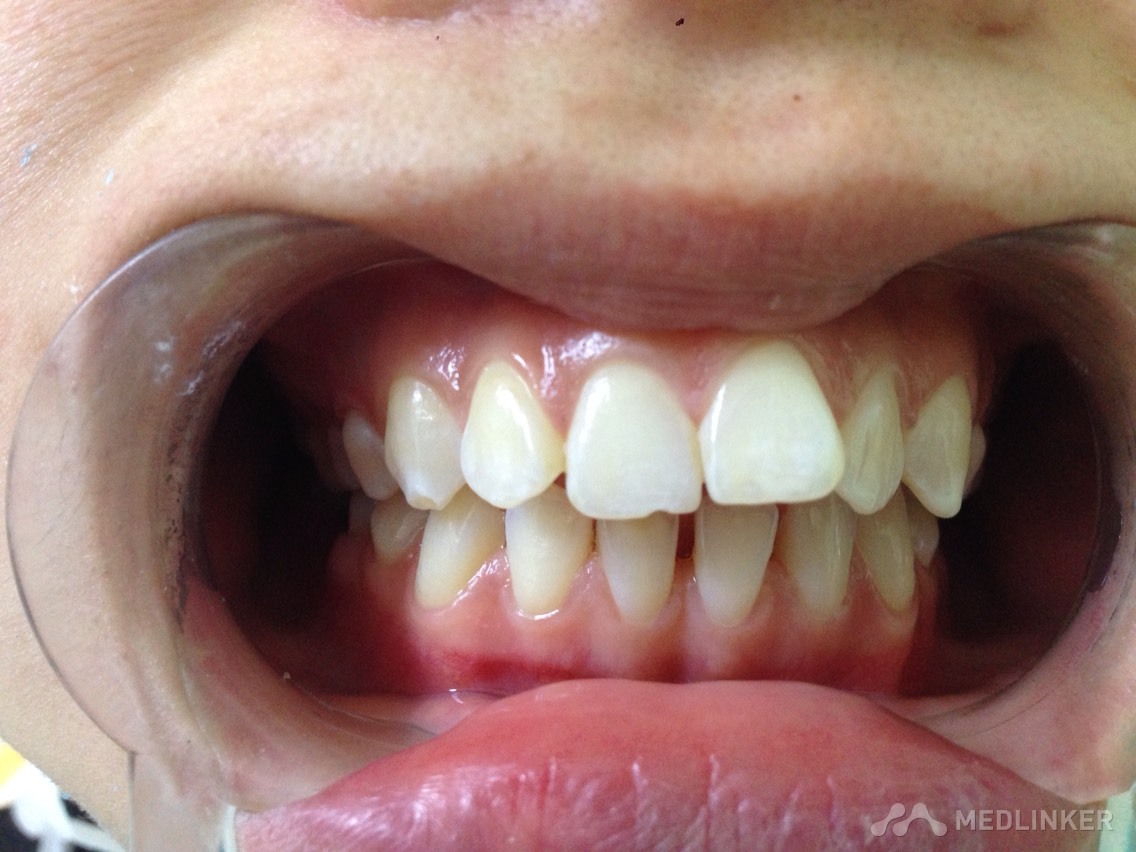

患者女,23岁,想做隐形无托槽矫正

上颌前牙牙列拥挤,下颌前牙散在间隙,下颌双侧第一磨牙缺失多年,开合